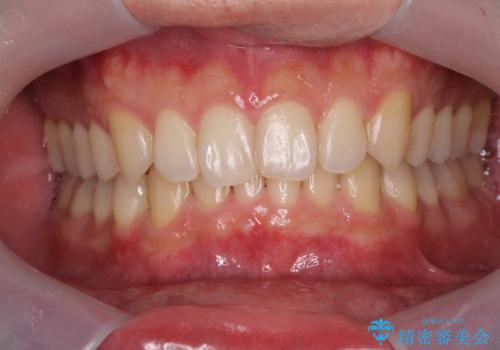

- 挙式を10日後に控えた患者様のホワイトニング施術をさせて頂きました。

違和感の無い白さにしたい…とのご要望があった為、施術中は患者様と白さ及び

知覚過敏の症状の有無を含め確認し慎重に進めました。

挙式を10日後に控えた患者様のホワイトニング施術をさせて頂きました。

知覚過敏の症状の有無を含め確認し慎重に進め患者様にも大変ご満足頂く事が出来ました。